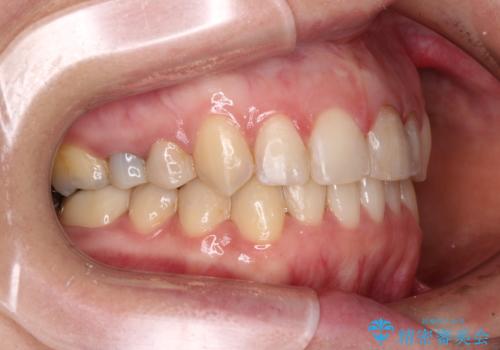

【モニター】前歯のデコボコと奥歯の虫歯 インビザライン治療と奥歯のセラミック治療

- 前歯のデコボコと奥歯の虫歯を気にして来院された患者様です。

主に下顎歯列全体の後方移動とIPR(歯と歯の間を削る)によってデコボコが解消するように設計し、インビザラインにより治療を行うこととしました。

矯正治療後半に下顎左右奥歯をセラミッククラウンにて補綴し、その後インビザラインによる歯列の仕上げを行うこととしました。

下顎前歯の叢生が速やかに改善されたため、1年3か月で治療を終えることができました。